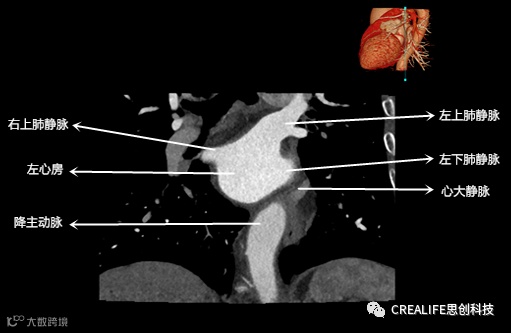

今天,跟大家分享心脏影像的经典层面——冠状位。通过冠状位的影像,我们可以从正位观察到心脏结构,看到主动脉的纵向剖面及冠窦交界处的心脏形态等多方位的心脏结构。现在,就让我们率先一睹“冠状位”的奇妙风采吧!